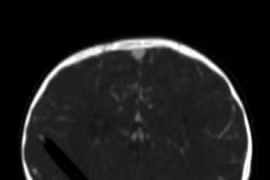

Bút chì 13cm đâm qua mắt vào não bé 19 tháng tuổi

(Kiến Thức)-Bé gái 19 tháng tuổi bị cây bút chì dài 13cm đâm xuyên qua mắt vào não trái do bị ngã từ trên ghế xuống khi đang vẽ đã bình phục hoàn toàn.